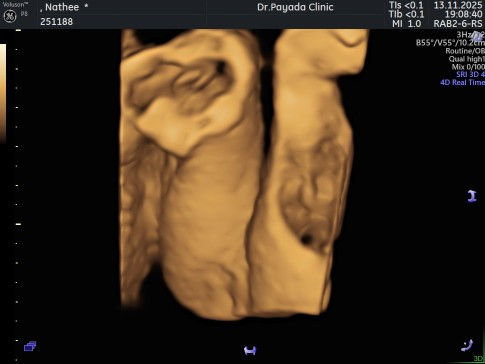

ผญ.หรือ ผช.คะ แม่ๆช่วยดูหน่อย😅

รูปอัลตร้าซาวด์นี้ สามารถเป็นผญ.ได้กี่เปอร์เซ็นคะ น้องหนีบเอาไว้ ซาวด์2รอบ คนละหมอ ก็บอกกว่าผญ.ค่ะ แต่แอบกลัวน้องมีไข่🤣